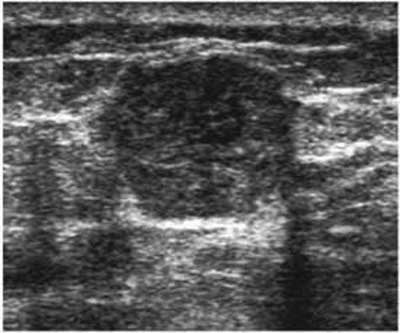

The target dataset was developed from 35 breast ultrasound scans that were segmented by an image-processing expert with extensive experience in breast lesion segmentation (the second author). The images, collected from the Web, are of different dimensions, ranging from to pixels (Figure 3, images resized for sake of illustration). These are the same images used to introduce EFIS originally [1].

Ultrasound images are generally difficult to segment, primarily due to the presence of speckle noise and low level of local contrast. It should be noted that the segmentation of ultrasound actually does require a complete processing chain, (including proper preprocessing and post-processing steps). However, the purpose of using these images was solely to demonstrate that the accuracy of the segmentation can be increased with the application of SC-EFIS.